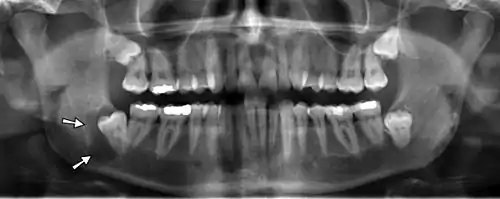

On an x-ray, cysts appear as radiolucent (dark) areas with radiopaque (white) borders.[7] However, cysts in maxillary sinus, also known as antrum, can appear radiopaque as the surrounding air absorbs fewer photons than the cystic fluid content.

Cysts are usually unilocular, but may also be multilocular. Sometimes aspiration (fine needle aspiration) is used to aid diagnosis of a cystic lesion; e.g., fluid aspirated from a radicular cyst may appear straw-colored and display shimmering due to cholesterol content.[5] Almost always, the cyst lining is sent to a pathologist for histopathologic examination after it has been surgically removed. This means that the exact diagnosis of the type of cyst is often made in retrospect, and definitive treatment can be made for the patient.